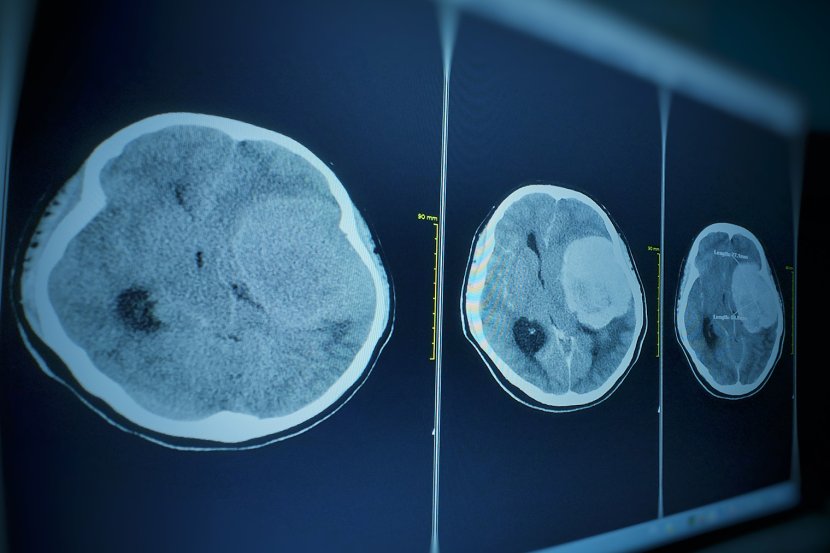

Veći meningiomi mogu da ometaju protok cerebrospinalne tečnosti i da dovedu do hidrocefalusa

Meningiom je tumor koji raste iz membrana koje okružuju mozak i kičmenu moždinu - meninga. Meninge se nalaze između mozga i lobanje i između kičmene moždine i kičmenih pršljenova. Meningiom nije tumor mozga, ali jeste najčešći tip tumora koji se formira u glavi. Većina meningioma raste veoma sporo. Mogu rasti godinama bez izazivanja simptoma. Uglavnom se slučajno dijagnostikuju.

Meningiomi ne napadaju direktno mozak, ali tokom rasta mogu da pritiskaju delove mozga ili kranijalne nerve i blokiraju apsorpciju cerebrospinalne tečnosti. Kranijalni nervi potiču iz mozga, moždanog stabla i deo su perifernog nervnog sistema. Sa vratnim kičmenim nervima učestvuju u inervaciji glave i vrata.

Veći meningeomi

Meningeomi manji od 2 centimetra najčešći su intrakranijalni tumori. Mogući su i multipli meningeomi. Tipični simptomi su glavobolje, problemi sa vidom, epileptični napadi, konfuzija.Veći meningiomi mogu da ometaju protok cerebrospinalne tečnosti i da dovedu do hidrocefalusa - proširenja komora mozga, koje se javlja usled povišenog pritiska u centralnom nervnom sistemu,  izazvanog velikom količinom likvora. Ovo stanje može da oteža hod i sposobnost pamćenja. Tumor može da deluje na čulo mirisa, vida, sluha.